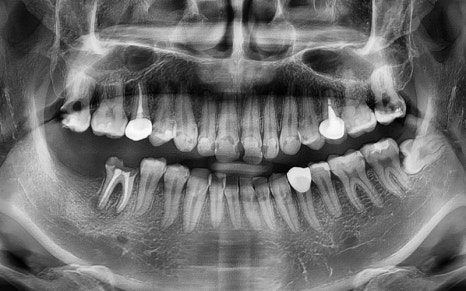

파노라마상에서도 성공적으로

치료가 진행 된 모습을 체크하실 수 있습니다.

현재 임플란트는

인공치근 부분인

픽스처만 식립되어 있는 상태로,

추후 크라운(보철물)을 올리는

보철과정까지 잘 마무리 해드리기로 했습니다.